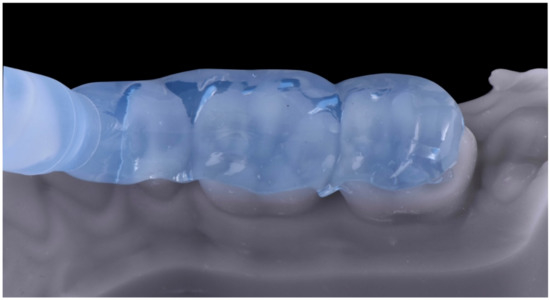

2.1. Planning Phase

2.2. Restorative Phase